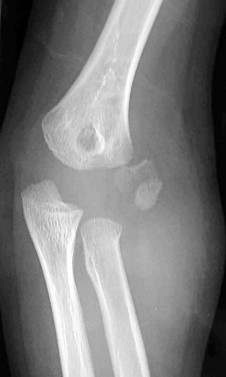

A 5-year-old boy presents with an extension-type Gartland III supracondylar humerus fracture after a fall.

On examination, his hand is well-perfused (pink) with brisk capillary refill, but the radial pulse is absent. What is the most appropriate initial management?